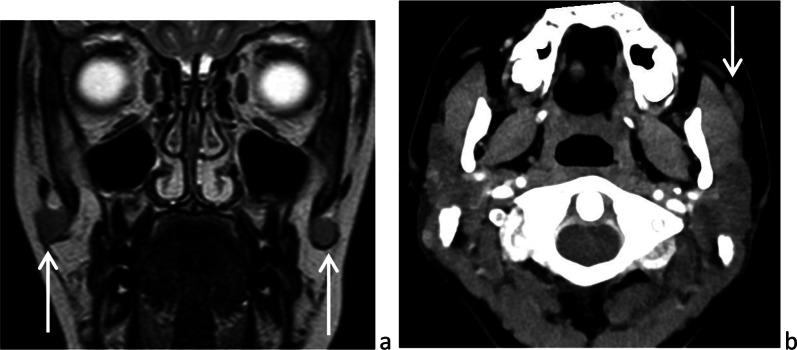

在婴幼儿及儿童时期,多种疾病可累及腮腺。急性或慢性炎症/感染性疾病最为常见。第一鳃裂畸形是先天性病变,通常在儿童期出现。肿瘤性病变多为良性,婴儿期最常见的是婴儿血管瘤,儿童期最常见的是多形性腺瘤。恶性肿瘤并不常见,黏液表皮样癌相对多见。腮腺浸润性疾病罕见,且具有一些儿科临床特点。本文对儿童期腮腺这些常见和不常见疾病及其影像学特征进行综述。